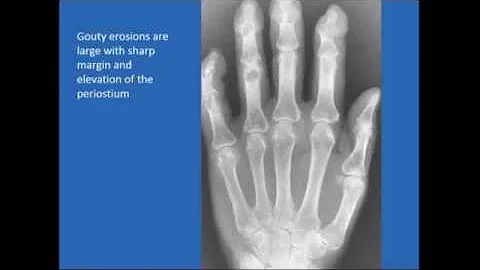

Gout And Pseudogout: What Are The Differences?, Antonelli, Md

Gout and Pseudogout: What Are The Differences? by Dr. Mary Ann Antonelli, Clinical Professor, Department of Medicine, ...